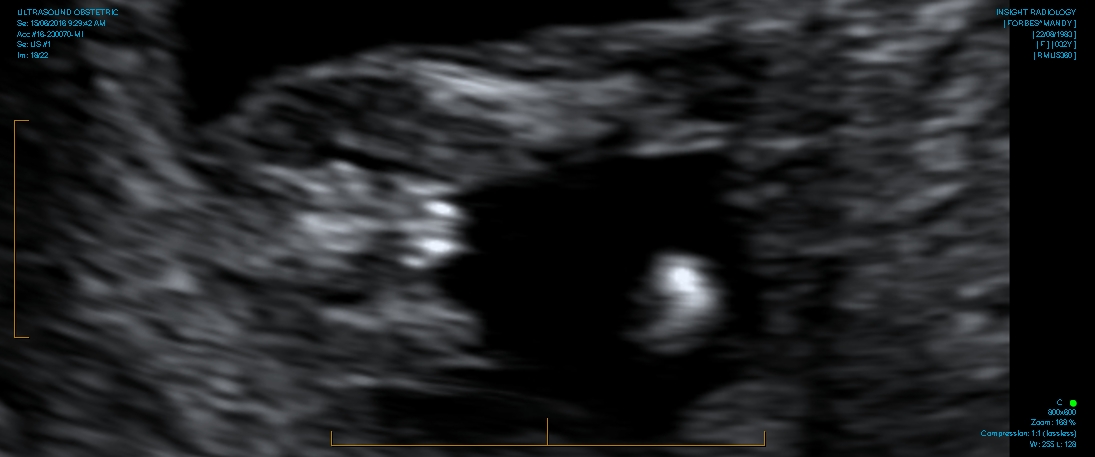

12 weeks 5 days

Looks girly!! But it is still early and I believe potty shots can be trusted more after 15 wks..

It's confirmed girl today! I'm over the moon